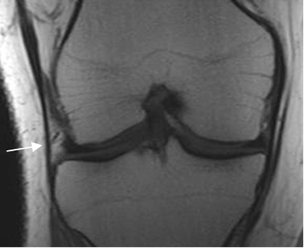

Los ligamentos colaterales unen el fémur distal, con la tibia y el peroné proximal. (Fig 20).

Fig 20. Ligamentos colaterales normales.

A y B: RM coronal en T1. LCL en A y LCM en B.